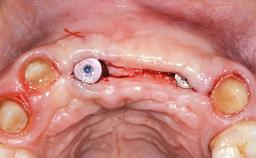

A 29-year-old woman was referred to our department for implant therapy. At the day of examination, a detailed Esthetic Risk Assessment (ERA) was performed (Martin and coworkers 2006). The patient was in good general health, but a heavy smoker (more than 20 cigarettes per day). When her midface had been injured in a severe car accident 10 years earlier, the dentition in the anterior maxilla was also affected. The injured anterior teeth (11, 21, 22) required endodontic treatment and were restored with crowns. Within a few years of the accident, the patient developed a considerable esthetic problem due to progressive recession of the gingiva in the area of the restored teeth. The local status demonstrated severe exposure of the root surfaces, especially of root 21, and black triangles between the three teeth. Thanks to her medium smile line, the patient was able to conceal the exposed root surfaces, but not the black triangles.